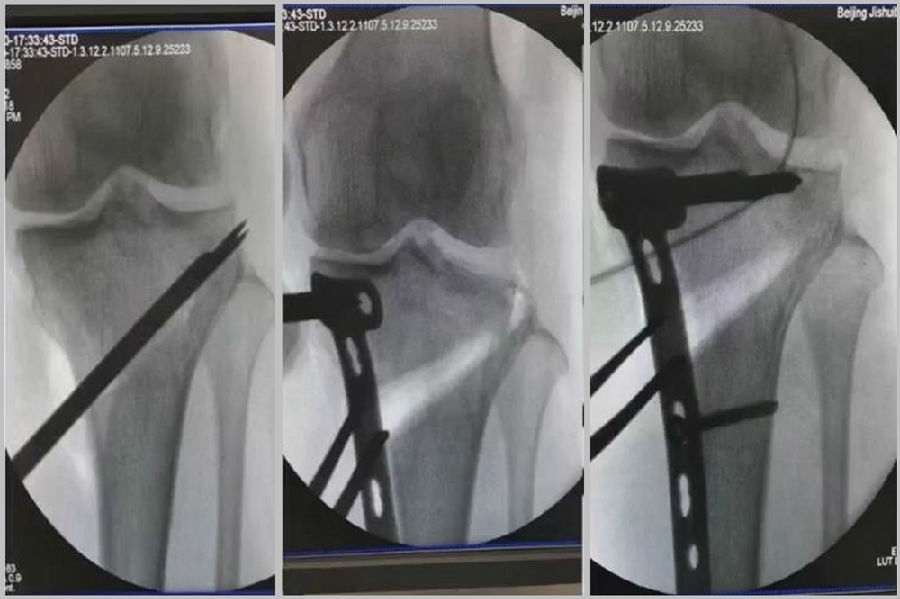

(3)Ⅲ型骨折

首先要把截骨撑开钳拿下来,此时骨折端会自动复位,然后再由外向内侧打入一颗拉力螺钉,将胫骨平台做临时固定,然后再进一步的用摆锯锯或是用骨刀打,保留1cm的合页,最后再进行撑开,做内固定。同样要求患者做结构植骨加延迟负重。

截骨偏前,截骨线过短;Ⅲ型骨折;保留1cm合页

结构植骨,外侧拉力钉固定